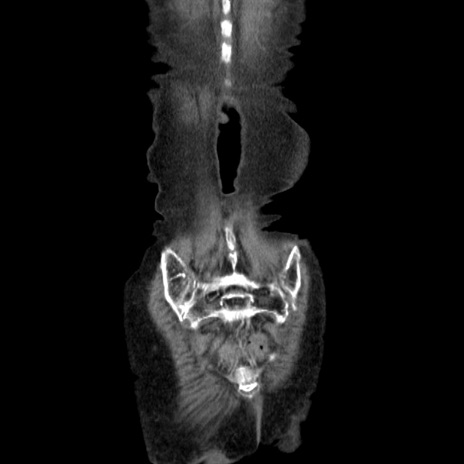

症例25(冠状断像)

【症例】80歳代女性

【主訴】胸のつかえ感

【現病歴】約9時間前に食後から胸のつかえた感じあり、嘔吐あり、来院。

【既往歴】胃癌(全摘)、胆摘、虫垂炎

【身体所見】心窩部に圧痛あり、反跳痛なし。

【データ】WBC 5700、CRP 0.05